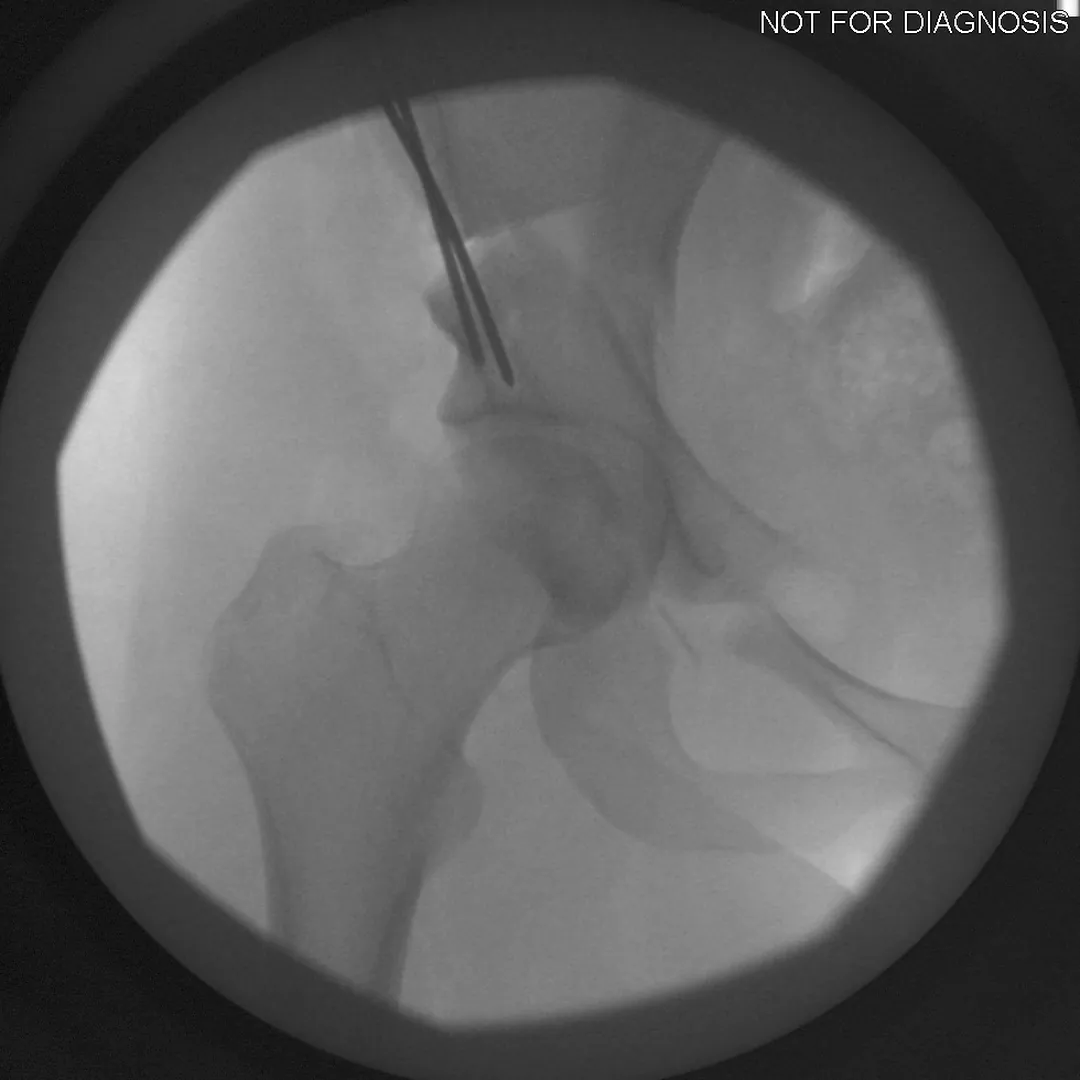

• Several controlled bone cuts are made around the hip socket

• The socket is repositioned and fixed with screws

• The hip joint itself is preserved